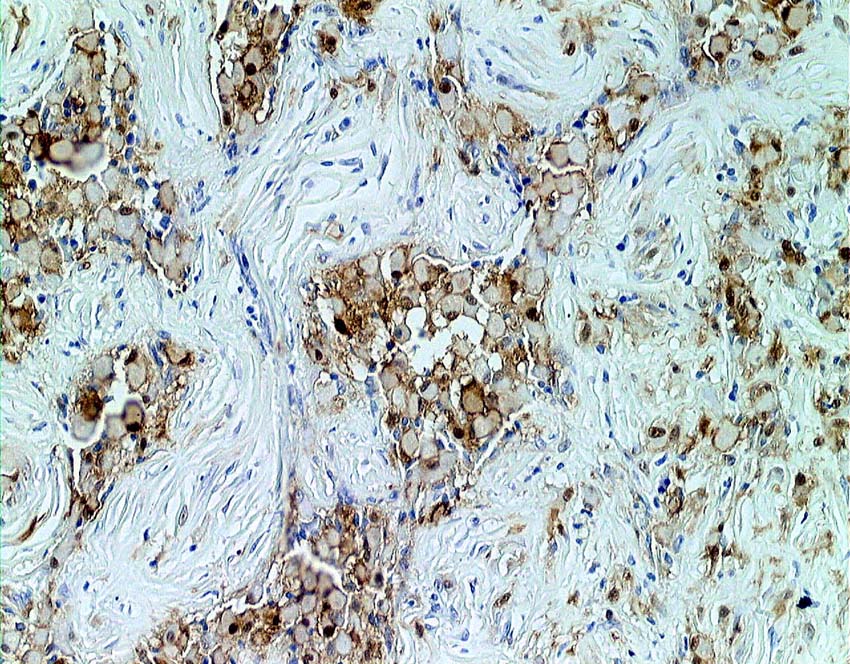

別な例の病理像です

左はHEで血管周囲に多様な細胞浸潤像があります,右はS-100です

CDa-1染色です